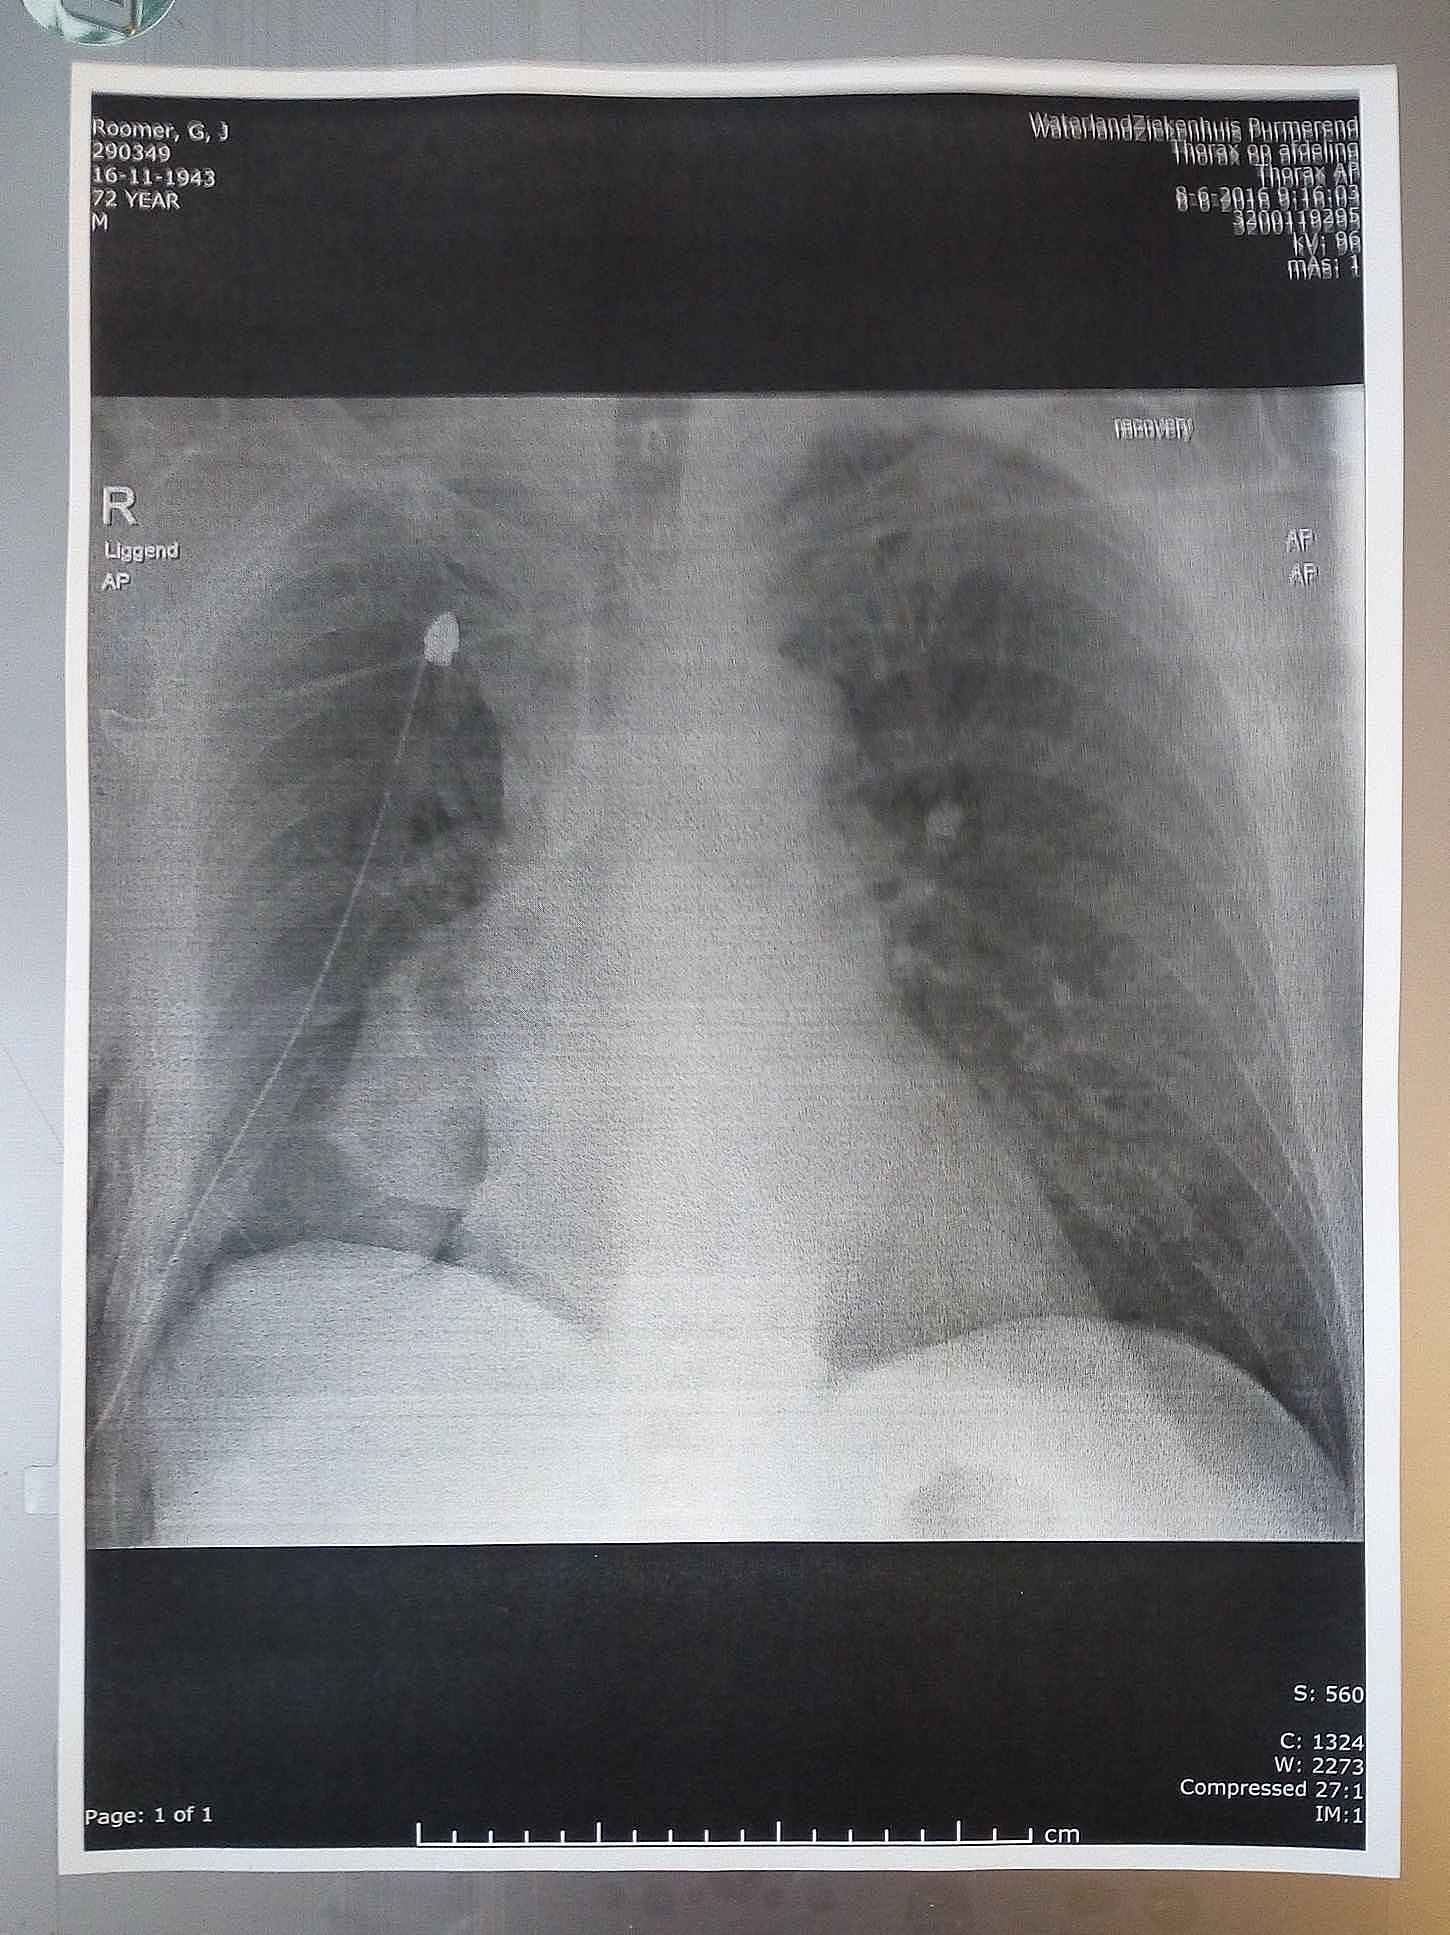

Half juni 2016